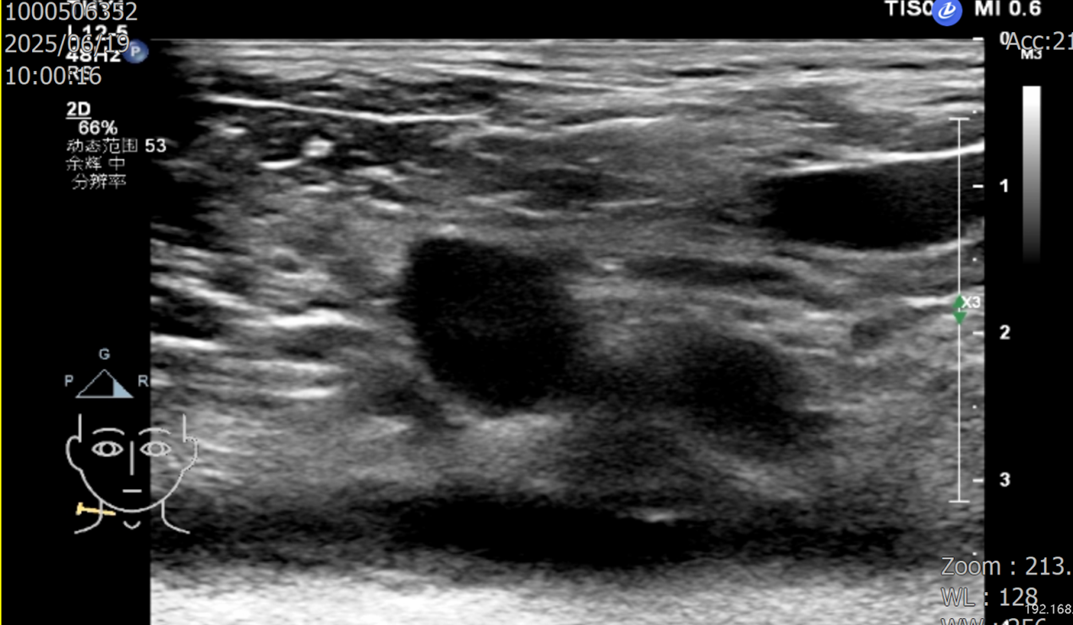

2023-02-10 胸部CT(图1):1.考虑左肺癌,肝、纵隔及左肺门淋巴结转移,左上肺动脉受侵,左肺上叶阻塞性肺炎。2.右肺上叶支气管扩张。

图1 CT(2023-02-10)